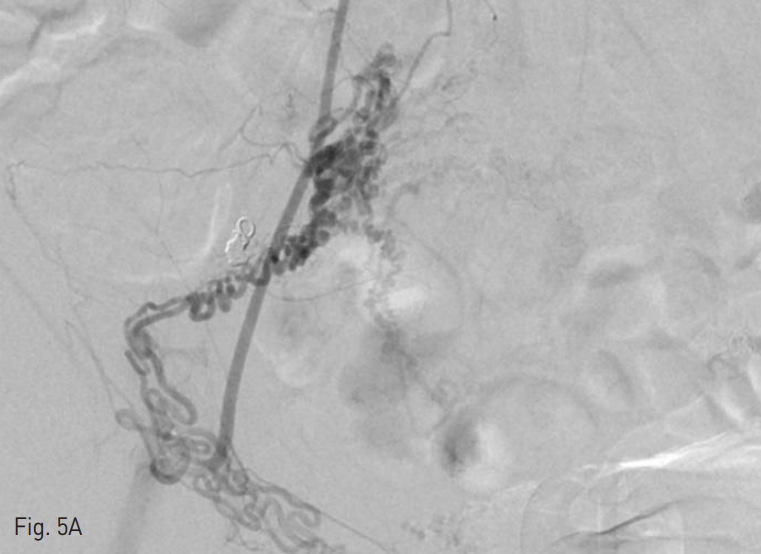

Fig. 5

Selective bilateral inferior epigastric arteriography (A~B) shows hypertrophy and tortuousity of both round ligament arteries.